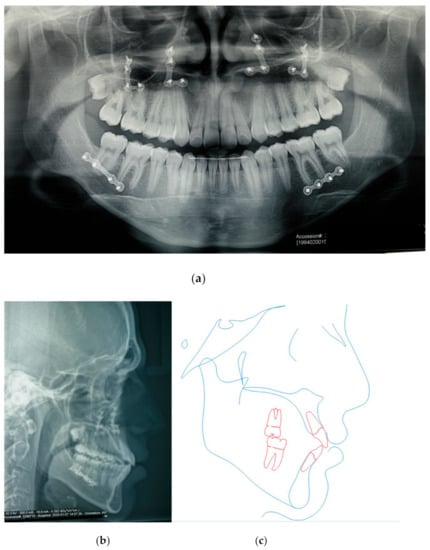

3.3. Postsurgical Orthodontic Treatment

3.4. Treatment Results